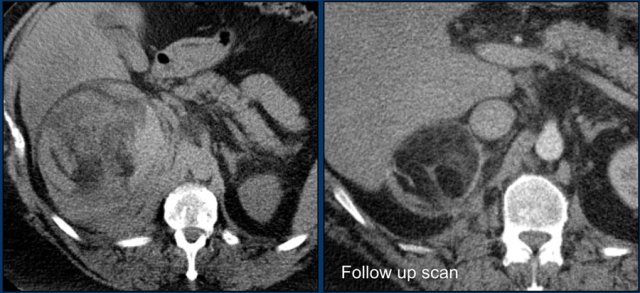

Axial and coronal image showing a large right myelolipoma with bleeding.

The image on the right is a follow-up scan.